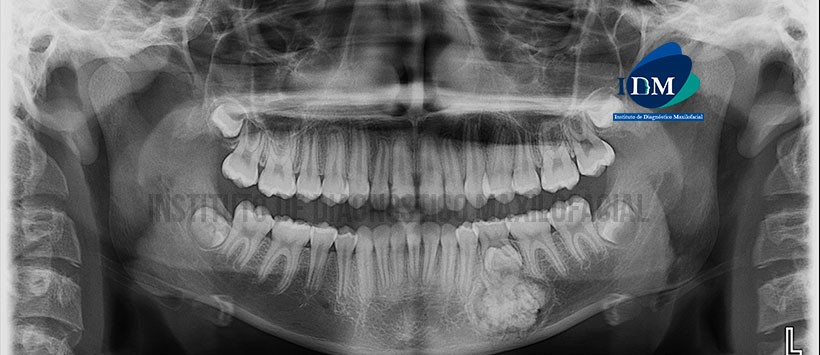

En la radiografía panorámica (Figura 1) se observa presencia de imagen radiopaca de densidad dentaria delimitada por un halo radiolúcido localizado en cuerpo mandibular izquierdo, condicionando la impactación de pieza 35.